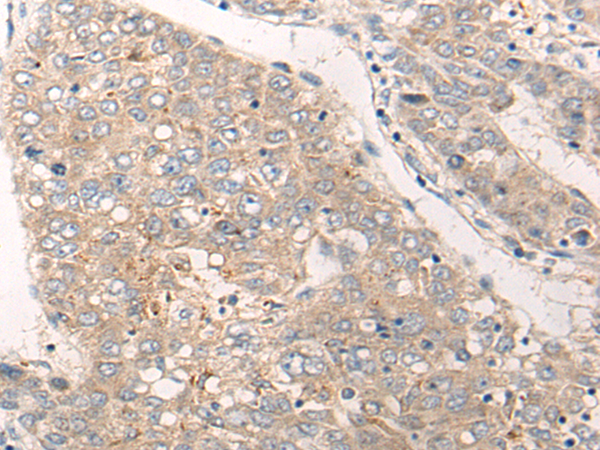

IHC positive control: |

Human liver cancer |

IHC Recommend dilution: |

20-100 |